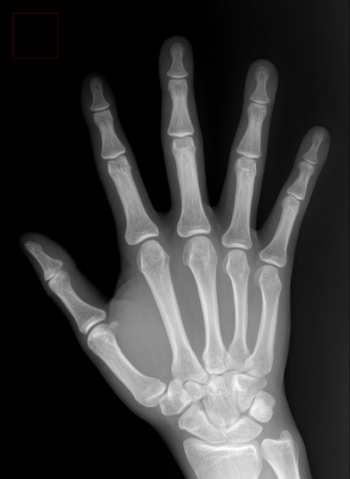

수근관증후군(손목터널증후군)은 손, 손바닥, 손목 저림 증상이 나타난다는 점에서 목디스크와 증상이 유사하다. 초기에는 손이나 손가락, 팔뚝의 힘이 약해지고 저리며 감각이 무뎌지는 증상이 나타나다가 점차 통증이 심해지고 힘이 약해져 결국 물건을 집고 주먹조차 쥐기 어려워진다. 척추만 전담으로 진료하는 경우는 간혹 이를 목디스크로 오인할 수도 있다.

수근관증후군과 목디스크는 치료법이 다른 만큼 병을 혼동하거나 잘못된 치료를 했다간 원인 질환을 더 악화시킬 수 있다. 이 경우 먼저 근전도 검사를 통해 손 저림의 원인이 목디스크인지, 손목터널증후군인지 확인해야 한다. 소요 시간이 짧고 검사법도 간편하다.